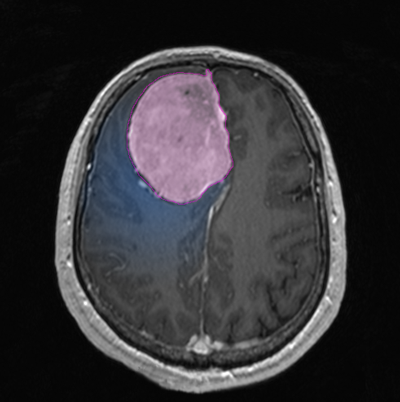

Θεραπεία Η θεραπεία των μηνιγγιωμάτων που προκαλούν συμπτώματα είναι κατά κανόνα χειρουργική, και αυτό γιατί αποτελεί τον πλέον άμεσο και αποτελεσματικό τρόπο να αποσυμπιεστεί ο εγκεφαλικός ιστός ή τα κρανιακά νεύρα τα οποία πιέζονται. Στα ασυμπτωματικά μηνιγγιώματα η θεραπευτική σύσταση γίνεται ανά περίπτωση και η απόφαση εξαρτάται από πολλούς παράγοντες, όπως η ηλικία του ασθενούς, το μέγεθος και η θέση του μηνιγγιώματος, τα απεικονιστικά χαρακτηριστικά του, οι πληροφορίες που υπάρχουν από παλαιότερες απεικονίσεις για το ρυθμό ανάπτυξής του, κα. Όταν η θέση των μηνιγγιωμάτων ή η γενικότερη υγεία του ασθενούς δεν επιτρέπει ασφαλή χειρουργική παρέμβαση, τότε μπορεί |

![]() |

να προταθεί η ακτινοχειρουργική, ή σε μεγαλύτερα σε μέγεθος μηνιγγιώματα, η στερεοτακτική ακτινοθεραπεία. Συνδυασμός θεραπειών, όπως χειρουργική και κατόπιν ακτινοχειρουργική σε τυχόν υπόλειμμα το οποίο δεν μπορεί να αφαιρεθεί με ασφάλεια, δεν είναι ασυνήθιστος. Παρακολούθηση μπορεί να συσταθεί σε επιλεγμένες περιπτώσεις ασυμπτωματικών μηνιγγιωμάτων, συνήθως αποτιτανωμένων, σε ασθενείς μεγάλης ηλικίας. 'Οπως προκύπτει από τα παραπάνω, η επιλογή του τρόπου και του χρόνου της θεραπείας είναι εξαιρετικά εξατομικευμένη για κάθε ασθενή. Δες και ενότητες: Εξαίρεση Όγκου Εγκεφάλου-Κρανιοτομία και Ακτινοχειρουργική γ-knife.